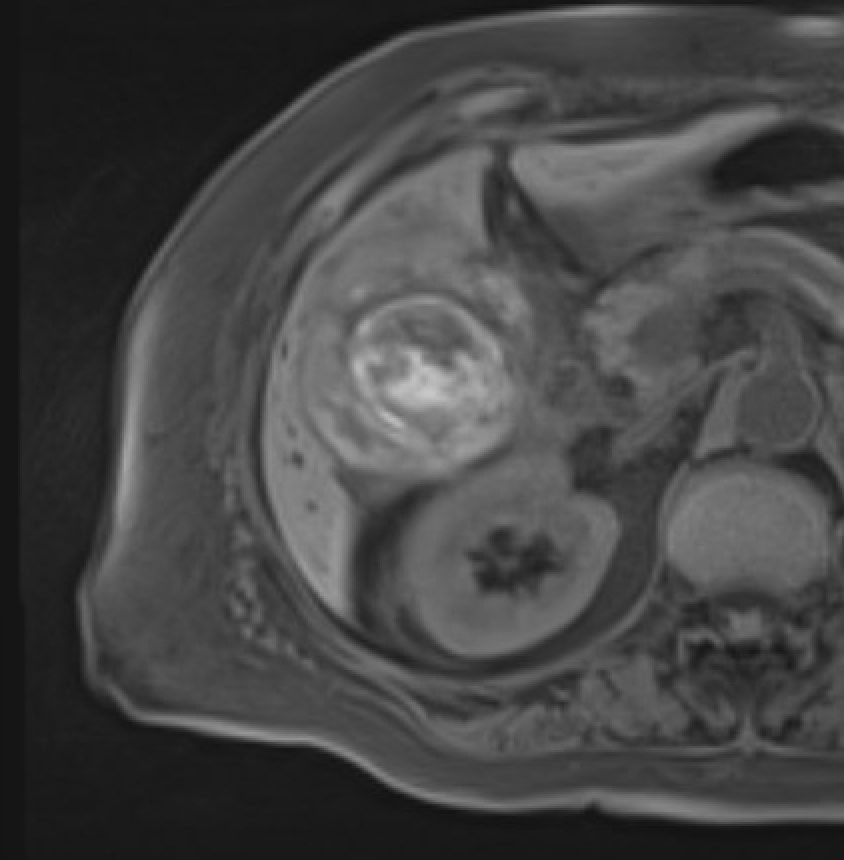

Ovarian torsion (pregnancy) Enlarged ovary with peripheral follicles and stromal edema on T2W. Pelvic ascites. Compare with contralateral ovary. Whirlpool sign of twisted pedicle

MRI showing ovarian torsion with enlarged ovary, peripheral follicles, and stromal edema on T2W

Ovarian torsion: enlarged ovary, peripheral follicles, stromal edema